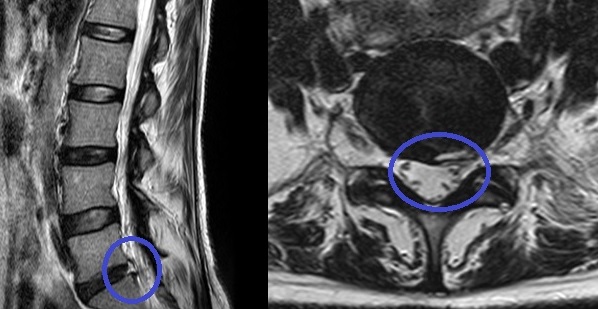

PELD (percutaneous endoscopic lumba discectomy) 내시경 레이저 디스크 수술은 허리 디스크로 인한 허리통증 및 하지 방사통을 완화하는 것을 목적으로 합니다. 허리 중앙에서 옆구리 10cm 정도 떨어진 위치에서 미세관을 디스크 속에 삽입하여 내시경을 이용해 모니터로 확인하면서 디스크에 병적인 수핵만을 제거하고 정상적인 수핵을 보존하는 수술입니다. 보존 요법과 수술 요법 사이에 있는 미세 또는 최소 침습 치료법으로 레이저를 사용하여 신경 압박으로 통증을 유발하는 수핵만을 제거하는 비관혈적 시술로 절개수술이 아니므로 신경, 근육에 손상을 주지 않습니다.

환자는 엎드린 상태에서 의사와 대화를 나누면서 국소마취를 합니다 국소 마취된 피부를 통해서 1mm 크기의 바늘을 영상증폭장치를 보면서 치료할 부위에 위치시킵니다 1mm 바늘을 통해서 가는 가이드를 넣고 점차 큰 가이드로 교체하여 넓혀서 7mm 크기의 내시경을 치료 부위에 위치 시킵니다 내시경을 통해서 탈출된 디스크 조각과 신경을 구별해서 보면서 신경을 구별해서 보면서 영상증폭장치로 수술 부위를 계속 확인하면서 탈출된 디스크 조각을 제거합니다